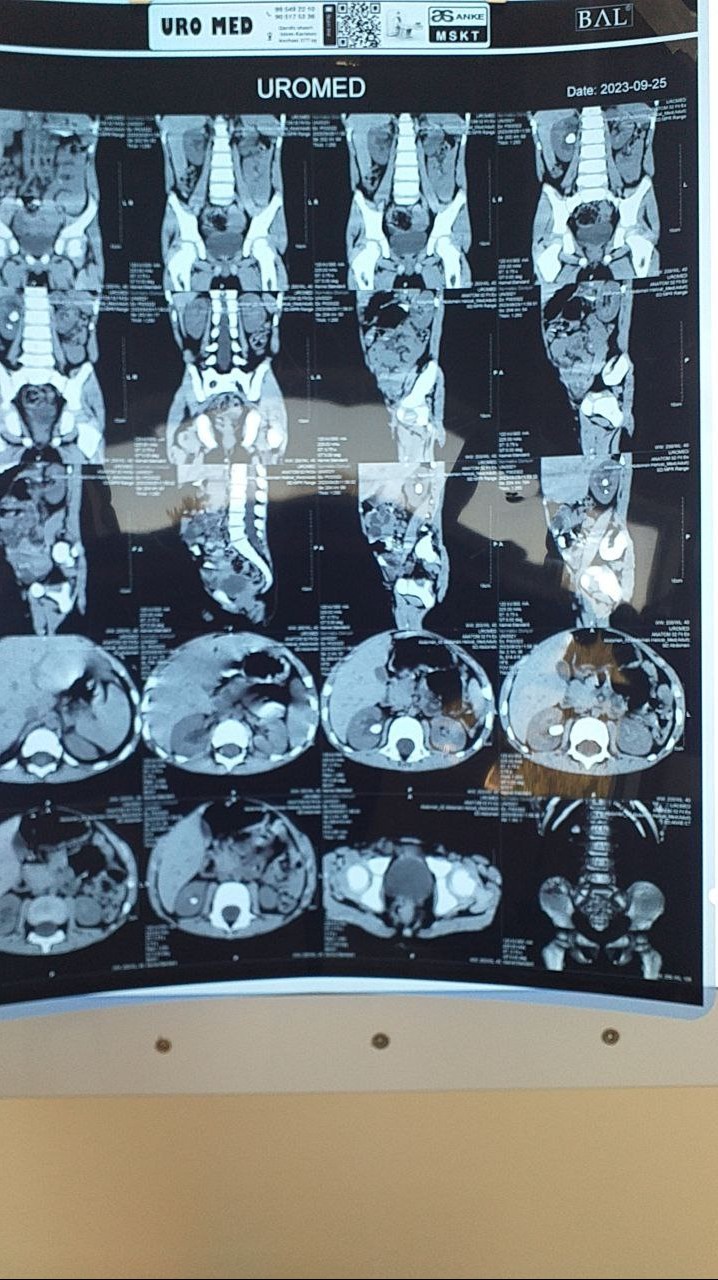

“Сийдик-тош касаллиги. Ўнг буйрак тошлари. Гидронефроз ўнгда. II даража” ташхиси билан муассасанинг урология бўлимига келтирилган Дониёржоннинг ўнг буйрагида 2 та тош борлиги тасдиқланди.

Жарроҳлар ингичка найча орқали боланинг буйрагидаги тошларни лазерда майдалаб, чиқариб олишди.